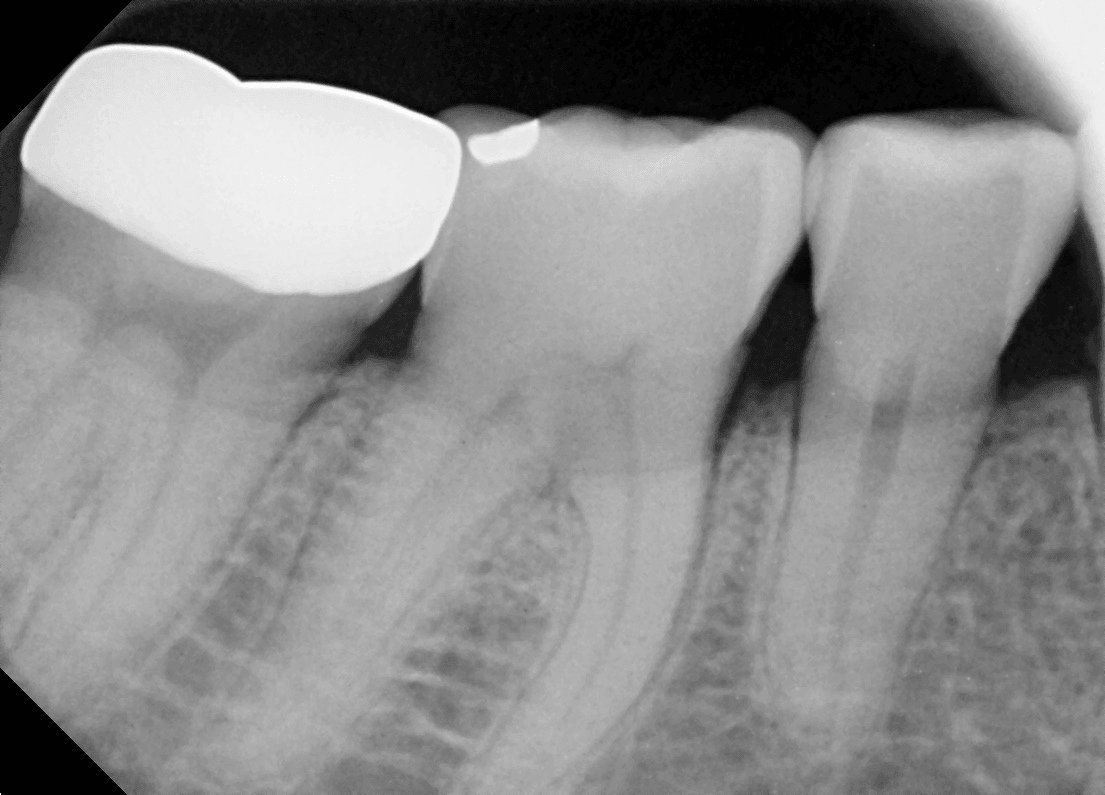

치과 마취 후 통증이 줄어드나요? (부산 30대 중반/남 치과 마취 통증 언제까지)

치과치료 받을 때 마취할 때 너무 무서워요.

치과치료기 처음인데 치과에서 마취하면 어떤 느낌이 나는지 무서워요.